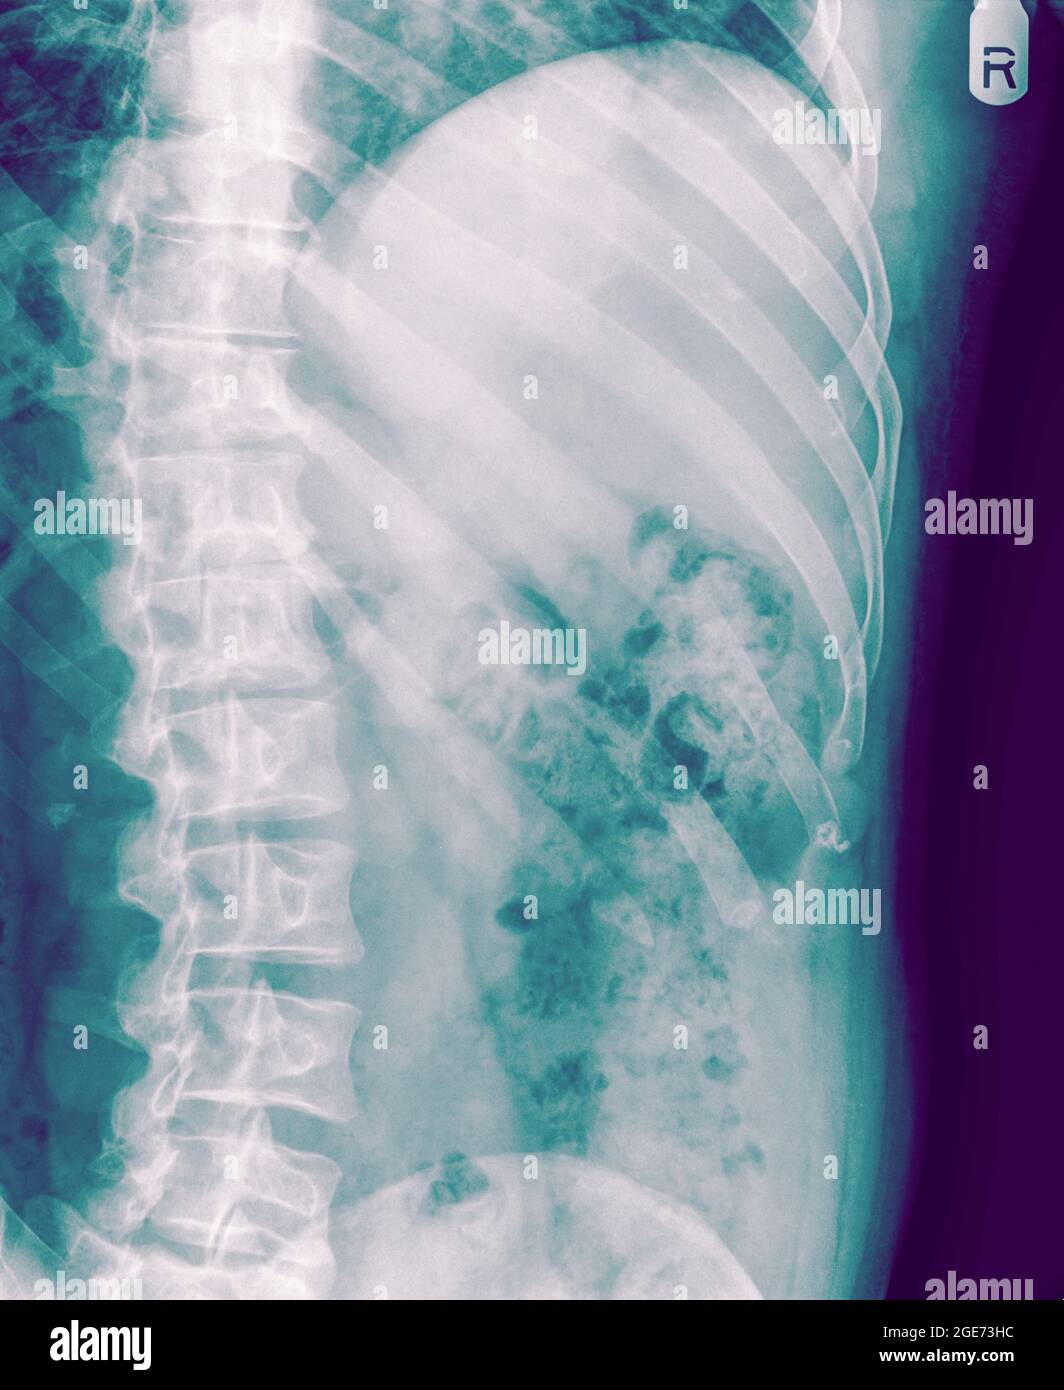

Patient with multiple rightsided rib fractures, flail chest Rib Fracture View Rib fracture is when one or more of the bones in your rib cage breaks or cracks. This is usually caused by: Broken or bruised ribs are usually caused by a fall, a blow to the chest or severe coughing. The most important thing is. Rib fractures are common injuries that occur most often following blunt thoracic trauma but can. Rib Fracture View.

Multiple rib fractures Image Rib Fracture View Rib fractures can range from a small crack caused by a random cough to a severe injury after trauma. Rib fractures can be relatively benign, but often may be a marker of concomitant injuries such as pneumothorax,. The most important thing is. What is a rib fracture? If you’ve ever had a rib fracture—a crack or an actual break in. Rib Fracture View.

CXR (Chest X r ay) showing fractures of left 6 th , 7 th and 8 th ribs Rib Fracture View This is usually caused by: Rib fractures can range from a small crack caused by a random cough to a severe injury after trauma. If there has been trauma with a. The most important thing is. Broken or bruised ribs are usually caused by a fall, a blow to the chest or severe coughing. Strong pain in your chest area,.. Rib Fracture View.